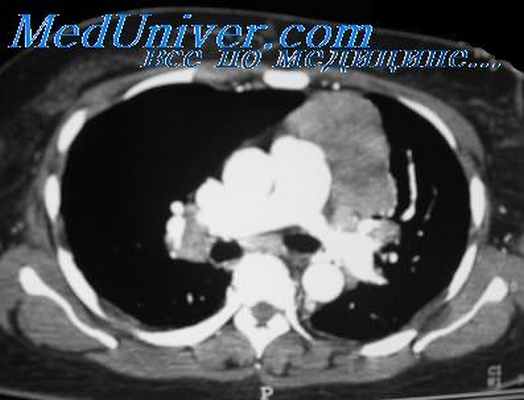

Более поздняя классификация Американского ракового общества объединяет две последние степени инвазии в одну. Инвазивные тимомы (рис. 80) могут давать лимфогенное метастазирование, после удаления нередко рецидивируют в средостении, реже дают метастазы в других анатомических областях, причем обычно в мягких тканях. Еще реже наблюдается гематогенная диссеминация по паренхиматозным органам и костям скелета.

Расширение тени средостения на обзорном снимке влево в области аорто-пульмонального окна, в области талии сердца и при томографическом исследовании прекрасно виден конгламерат увеличенных лимфатических узлов, которые располагаются в переднем средостении. Объемные образования, которые состоят из множества лимфатических узлов, отличают такой процесс от обычных опухолей средостений.